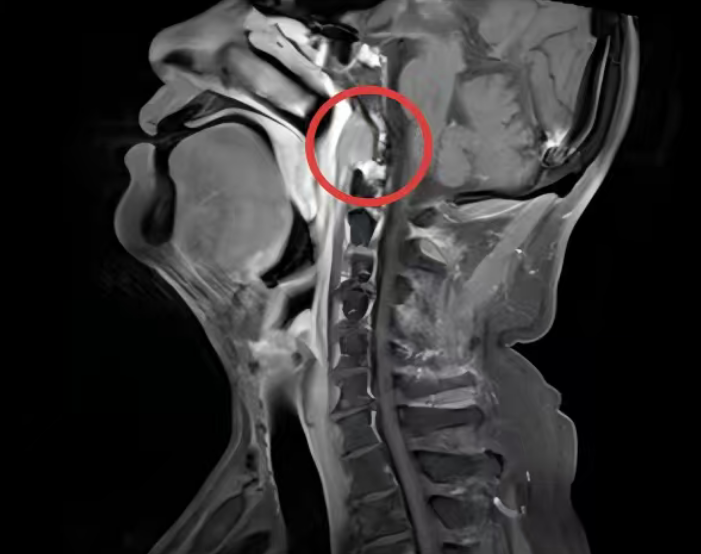

患者为74岁男性,既往接受鼻咽癌根治性放射治疗。本次随访复查MRI提示:右侧椎前间隙出现软组织结节,并侵犯头长肌;PET-CT高度怀疑肿瘤转移。

为进一步明确病理性质,门诊行电子鼻咽镜检查并尝试活检,但因病灶位置深在、解剖结构复杂、常规路径难以抵达核心区域,未能取得阳性结果。